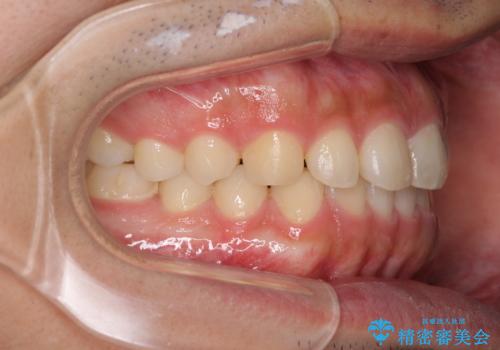

インビザラインによる、すきっ歯の改善

- 前歯がすきっ歯であることを気にして来院された患者様です。

下の前歯がほとんど隠れてしまうくらいの深い咬み合わせであったので、インビザラインを用いて、咬み合わせの高さを改善しながら隙間を閉じていくこととしました。

咬合力で上の前歯が前方に押し出されるようにして隙間ができていましたが、矯正治療により全て閉じることができました。

深い咬み合わせも多少改善され、隙間も閉じたことで、前方に出ていた前歯が引っ込んだため、口も閉じやすくなったとのことでした。